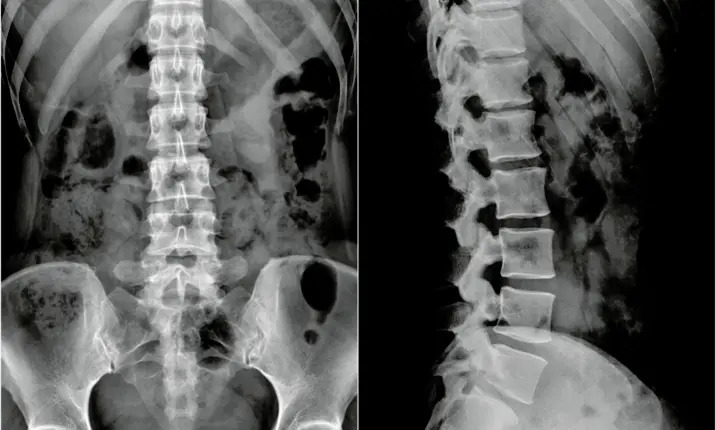

If you suffer from back pain and stiffness in the back that is so bad you have difficulty using the bathroom, it could be a sign that you have ankylosing spondylitis (AS), an arthritic condition that causes inflammation of the spinal joints.

It is important to diagnose AS in its early stages, when the condition is confined to the lower back and spine.

Once the inflammation progresses, it starts affecting the entire spine as well as the hips and the knees. In the most severe cases, the bones of the spine fuse together, impairing its flexibility and occasionally causing breathing difficulties. This phase of the disease is not reversible and, in extreme cases, can lead to immobility.